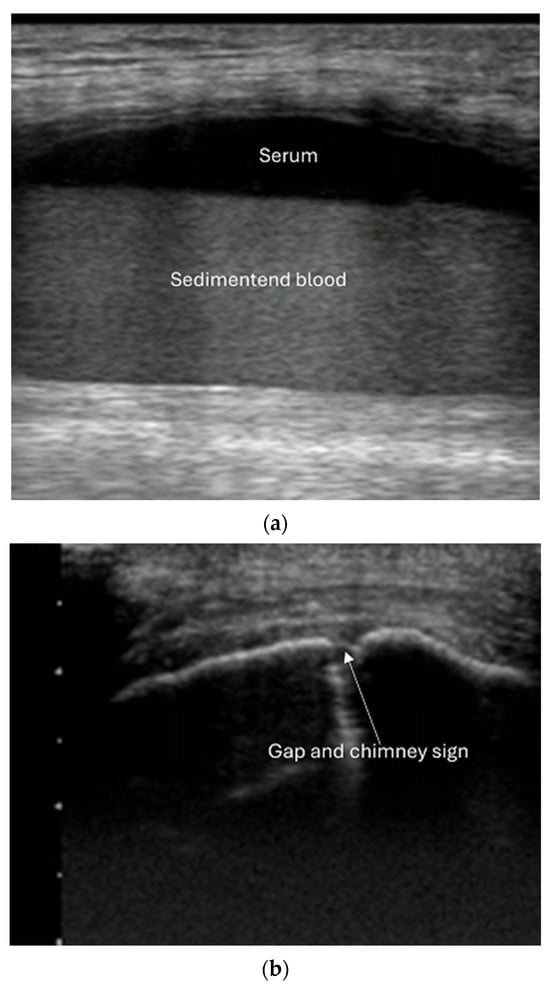

- Reverberation artifacts within or adjacent to the fracture gap (also known as the “chimney sign”): these repetitive echoes are caused by ultrasound waves reflecting off the fracture surfaces.

- Joint effusion and liphemarthrosis: fluid accumulation within a joint, sometimes containing fat droplets, which often indicates an intra-articular fracture.